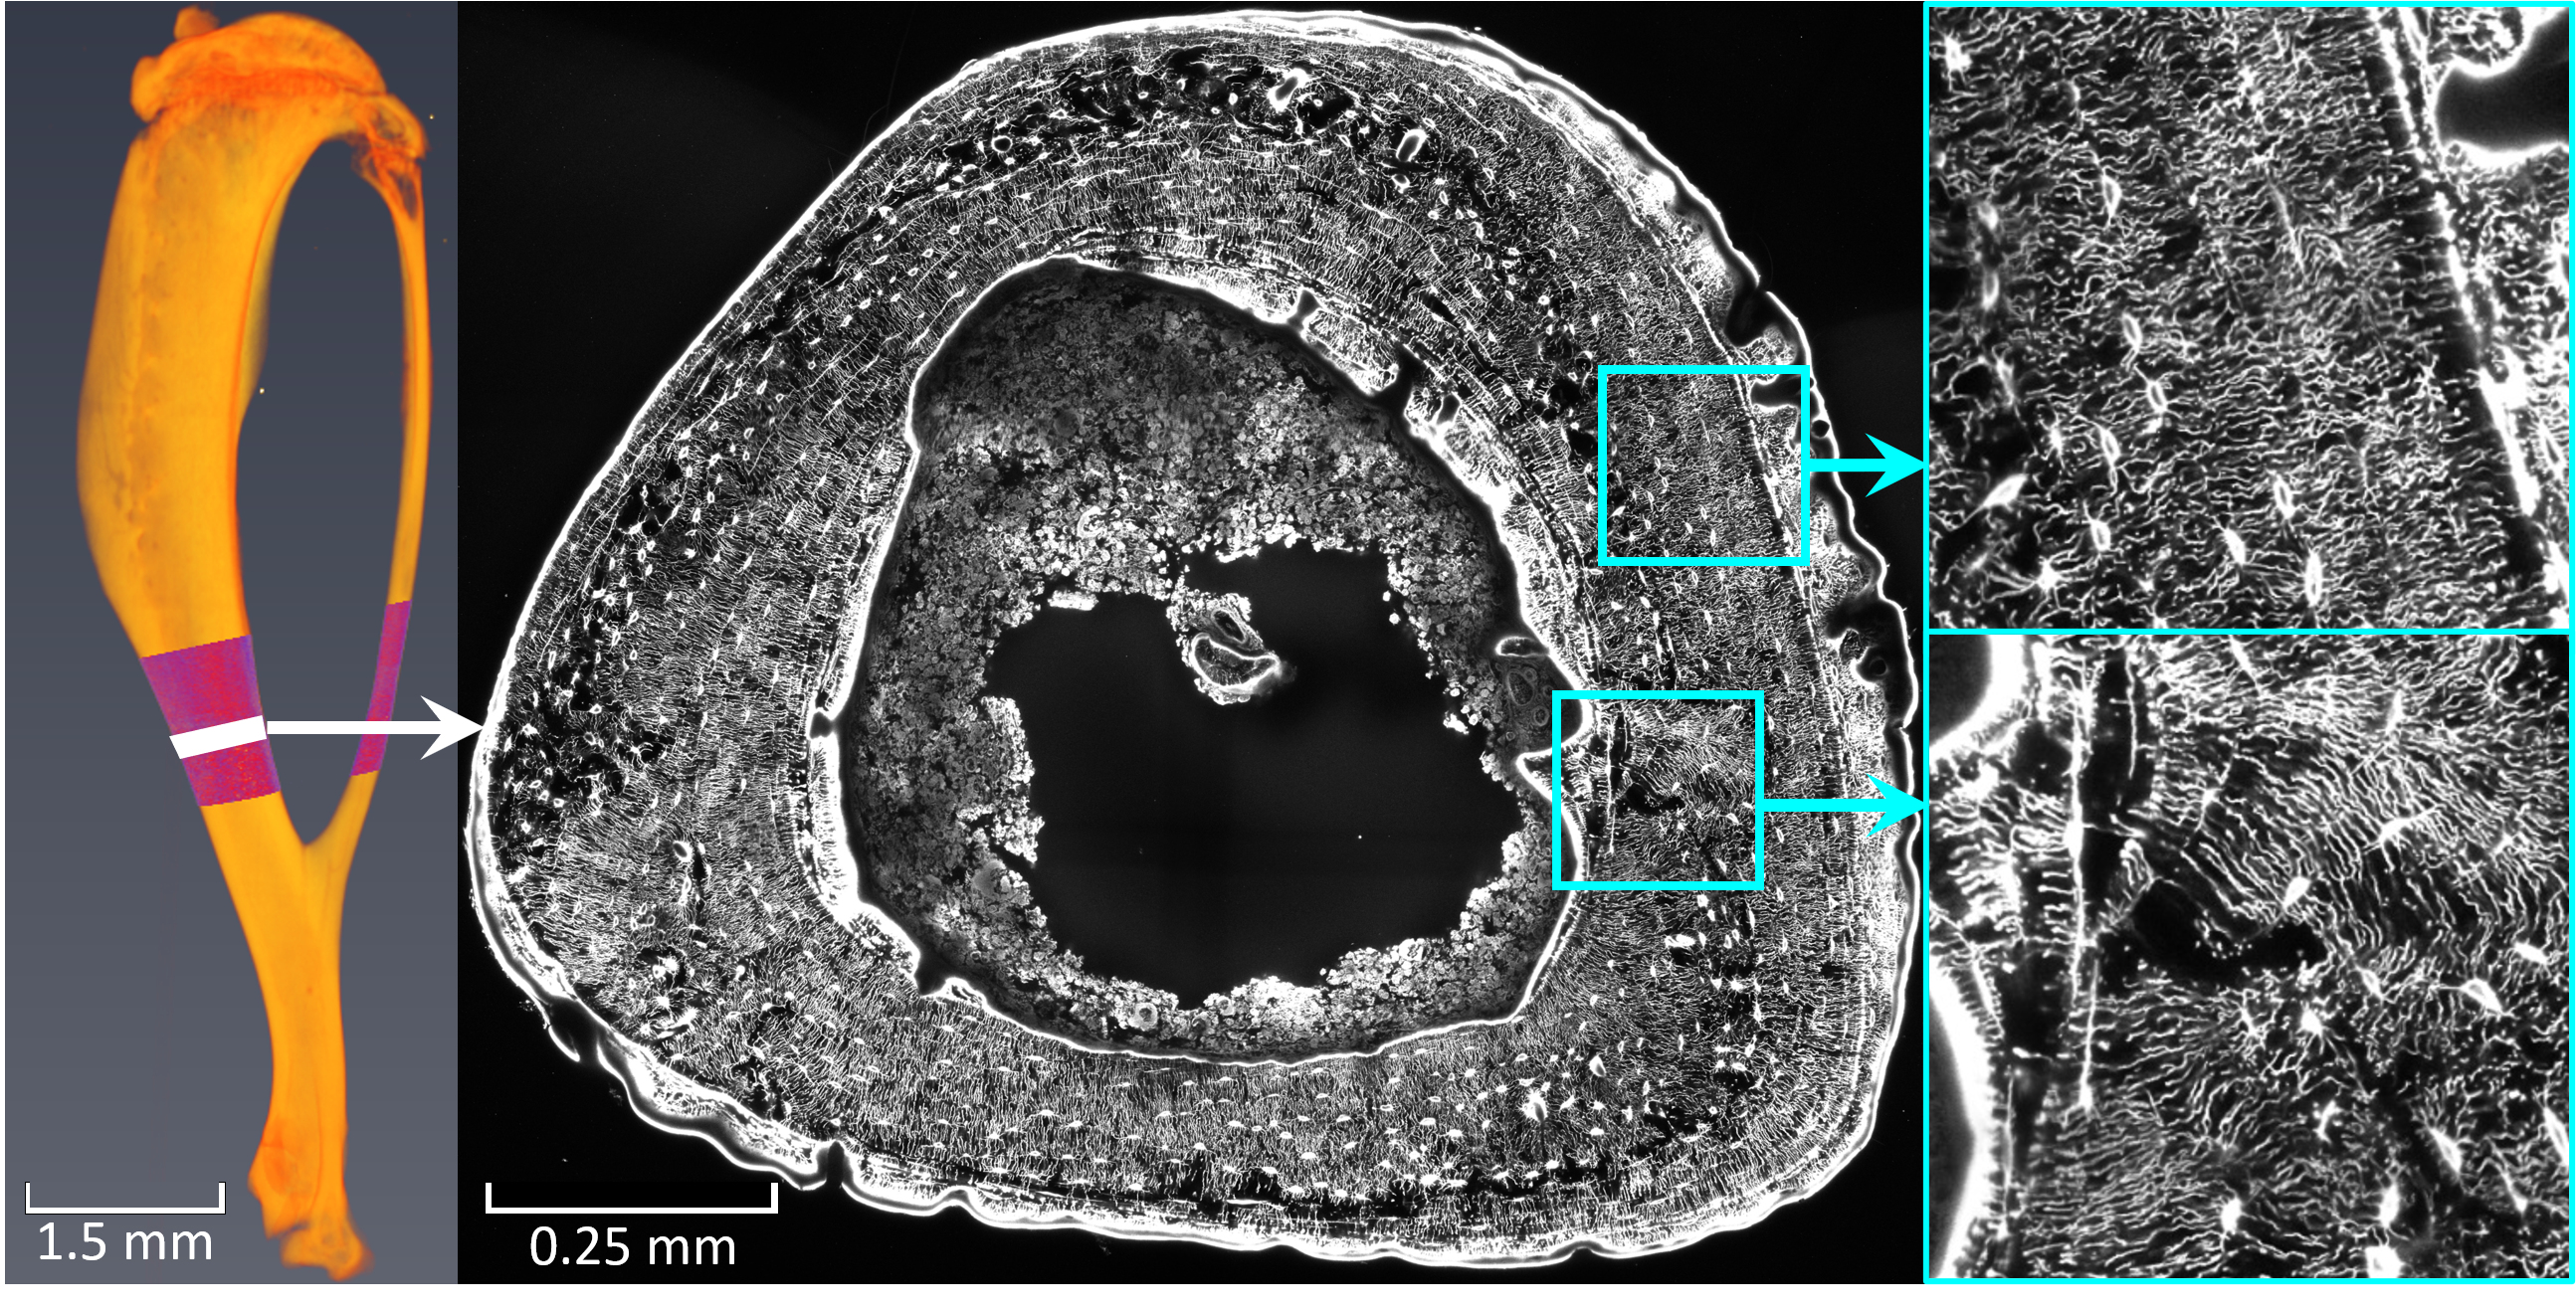

Our bones have so-called mechanosensors that react to pressure and communicate with each other. “These sensors enable that bone is formed where it is mechanically necessary and broken down elsewhere," says Richard Weinkamer from the Biomaterials Department. In their research they have come a decisive step closer to solving the mystery of where these mechanosensors are located: Hidden within a structure of canals inside the bone, a cell network "senses" external bone stress.

This works by translating the mechanical loading into a fluid flow through this fine canal network. There are similarities between the examined network and the neural network in the brain. It may be possible to draw conclusions about diseases such as osteoporosis or arthrosis, where the network has a modified architecture.

Bones can be trained like muscles. In the course of the study, researchers in Montreal examined mouse bones that had undergone controlled "bone training". In Potsdam, Weinkamer and his team used a scanning laser microscope to obtain 3D images of the cell network in the trained bones. The image data was used to analyze and evaluate networks with millions of canals by means of computer simulations that calculate the fluid flow through the network: "Based on our results, we are convinced that the bone cells within the networks can perceive the fluid flow, communicate with each other and thus pass on information such as 'need of bone growth' to other cells," says Alexander van Tol. He adds: "The examined mice reacted differently to bone training. A mouse that produced particularly little new bone has a network whose architecture allows only a slow flow of fluid". He adds: "We therefore believe that the same applies to humans: Bone can be strengthened particularly well through physical activity if the network structure within the bone 'plays along'. This study was the first to not only analyze the network architecture, but also to evaluate the quality of this architecture in terms of the perception of mechanical stimuli.